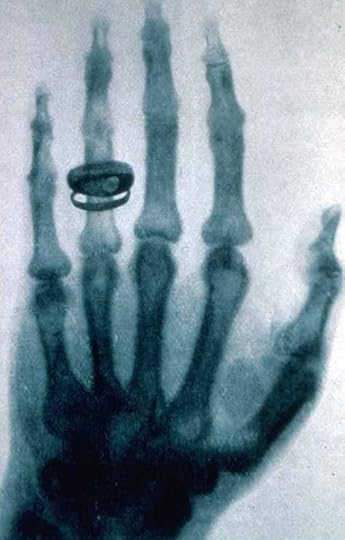

Bertha Roentgen���s hand x-rayed by Wilhelm Roentgen

In his six-week marathon research, Roentgen discovered that x-rays could penetrate materials such as wood, flesh, and a 2,000-page book. However, more dense materials such as metals and bone allowed much less, if any, penetration. He also discovered that photographic plates could be exposed by the x-rays. Three days before Christmas 1895, Roentgen took his wife into his lab and recorded the first (and perhaps most famous) x-ray of part of a person. The bones in Bertha Roentgen���s hand are clearly visible, as is the ring on her hand. Both of the Roentgens��� exposure to x-rays while this picture was being taken must have been tremendous. Today, x-ray machines carefully aim the rays so that only the area of interest is exposed. Over the years, special film and digital detectors have been developed so that only a very small amount of exposure produces the desired result. Roentgen had none of that. He had, at best, a very crude point and shoot x-ray device.

See Your Bones Everywhere, Even in Shoe Shops

On December 28, Roentgen submitted a paper, ���Ueber eine neue Art von Strahlung��� (On a New Type of Rays) to the Proceedings of the W��rzburg Physical-Medical Society. It included the picture of Frau Roentgen���s hand and quickly became a sensation worldwide. The medical implications were immediately recognized, and by May 1896, a handbook Practical Radiography had been published. However, it took a while for the value of x-rays to be fully understood. Tragically, it also took quite a while for the dangers of x-rays to be understood. Many people suffered damage and even death because their exposure to x-rays.